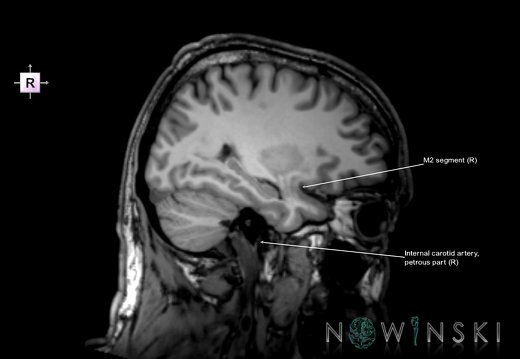

G6.T15.2.V2.P30.Intracranial arteries–Triplanar

G6.T15.2.V2.P30S.Intracranial arteries–Triplanar